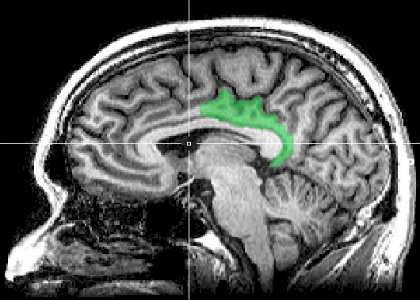

The question that Duke University graduate student Sarah Heilbronner wanted to resolve was whether this brain region, called the posterior cingulate cortex, or PCC, actively dampens cognitive performance, say by allowing the mind to wander, or is instead monitoring performance and trying to improve it when needed.

The PCC connects to both learning and reward systems, Heilbronner said, and is a part of the “default mode network.” It lies along a mid-line between the ears, where many structures related to rewards can be found. “It’s kind of a nexus for multiple systems,” said Heilbronner, who is currently a postdoctoral researcher in neuroanatomy at the University of Rochester.

Image Source: The image is credited to Geoff B Hall and is in the public domain.